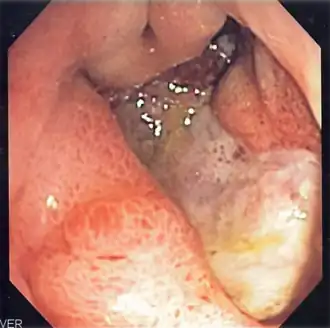

Endoscopic image of a posterior wall duodenal ulcer with a clean base, which is a common cause of upper GI hemorrhage. -